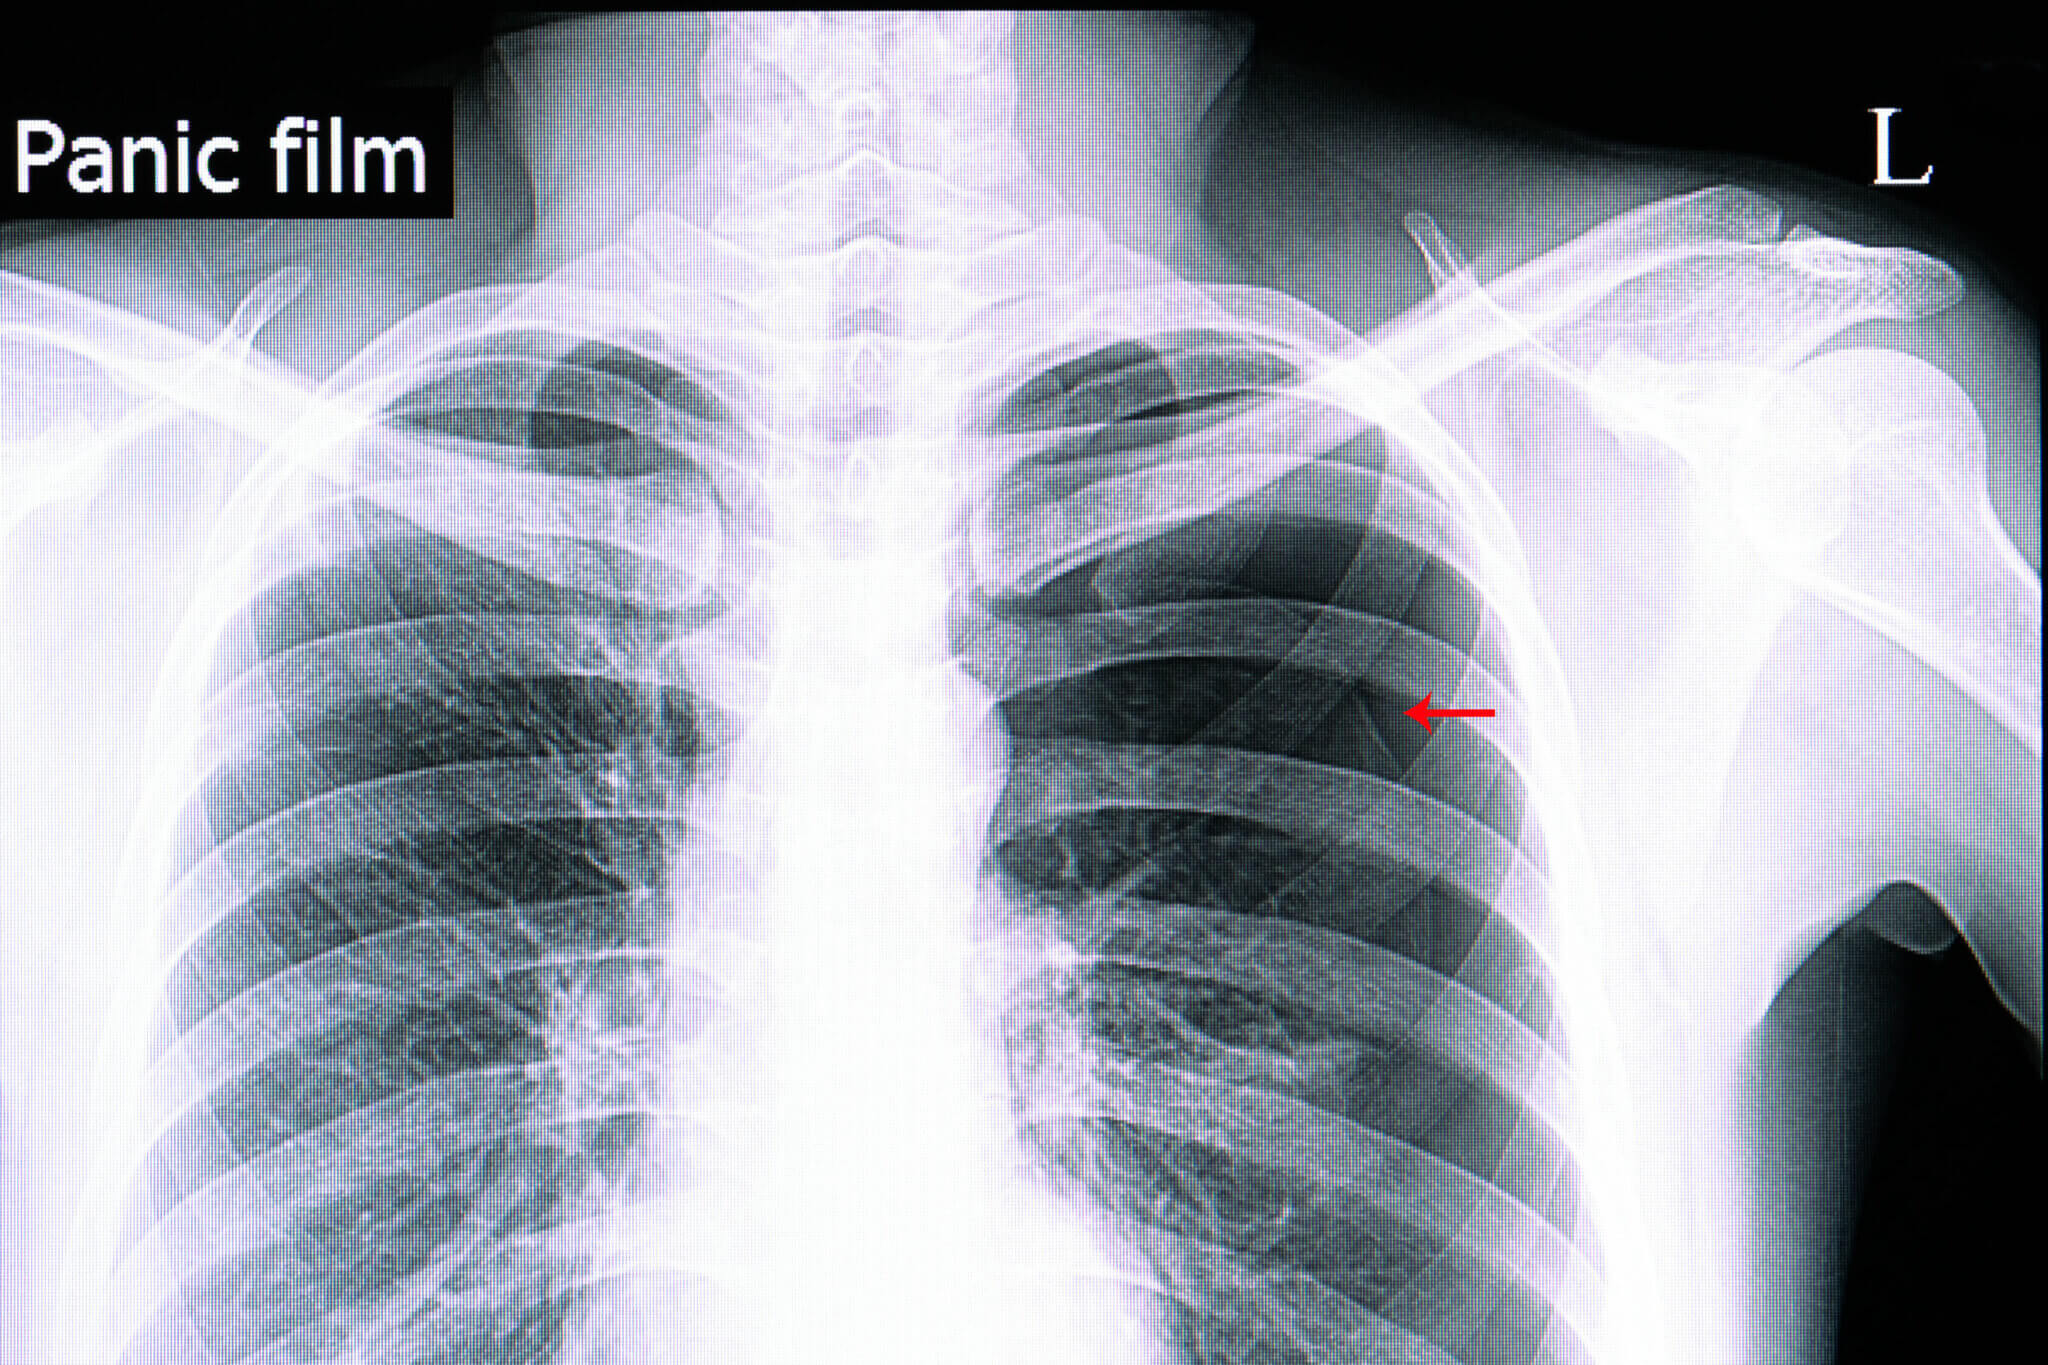

PNEUMOTÓRAX HIPERTENSIVO COMO IDENTIFICAR NO RX YouTube